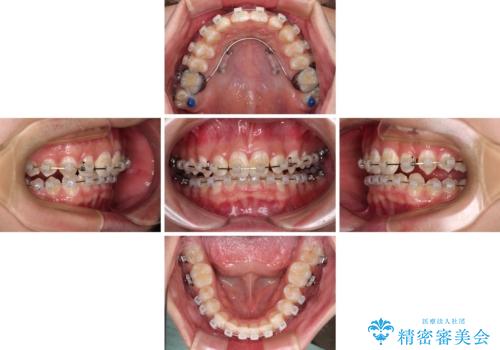

- クリアブラケット

このような咬み合わせの場合、治療期間は2年以上がかかることが一般的で、3年程度かかることもありえるケースです。

強く深い咬み合わせにより下顎装置は頻繁に脱離するため、治療期間が長くなりますが、予定通りに終了させることができました。